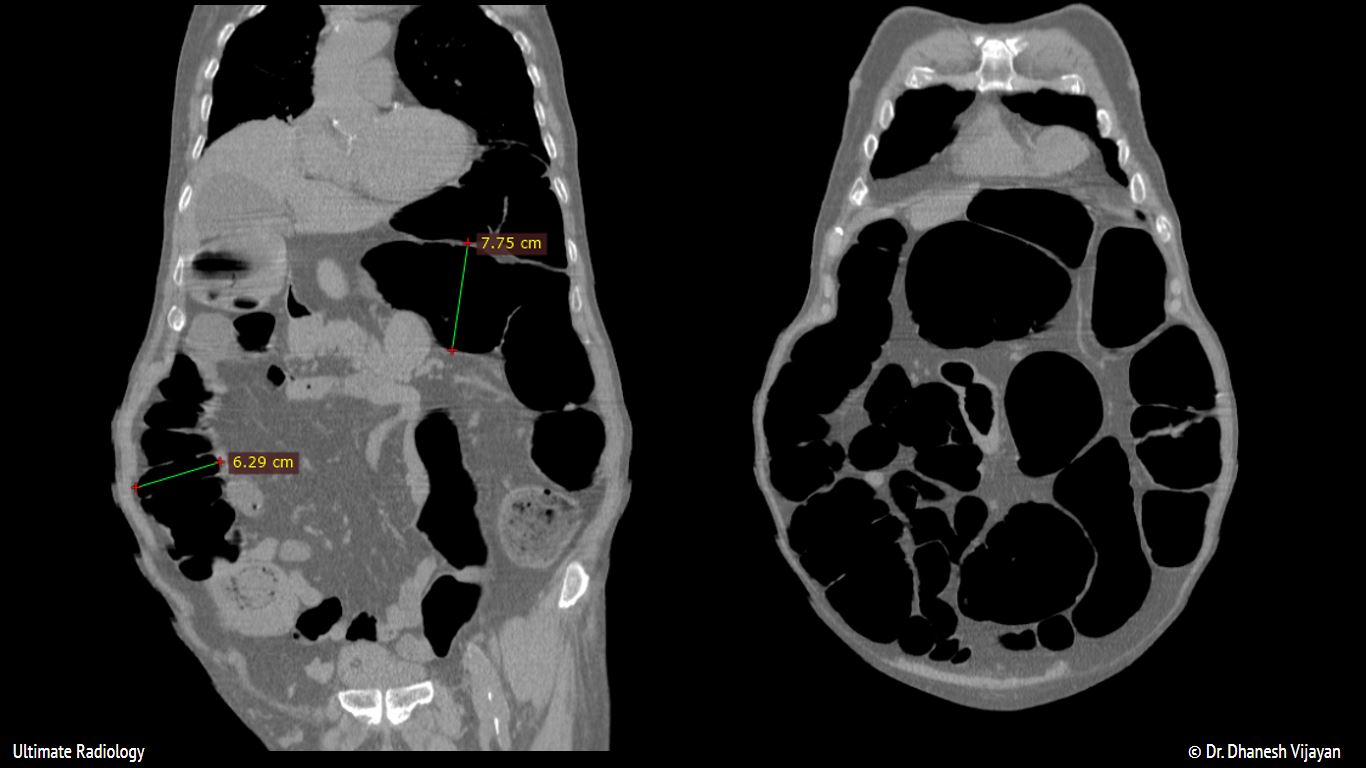

From ultimate-radiology.blogspot.com

Ultimate Radiology Ogilvie Syndrome or Acute Colonic Pseudo Obstruction Ogilvie Syndrome Etiology The exact cause isn’t fully understood, but scientists believe it results from a dysfunction of your autonomic. Patients presenting with ogilvie's syndrome have underlying medical and surgical conditions predisposing them to the syndrome. In some cases the small bowel may also be involved. Ogilvie Syndrome Etiology.

Ultimate Radiology Ogilvie Syndrome or Acute Colonic Pseudo Obstruction Ogilvie Syndrome Etiology Patients presenting with ogilvie's syndrome have underlying medical and surgical conditions predisposing them to the syndrome. In some cases the small bowel may also be involved. The exact cause isn’t fully understood, but scientists believe it results from a dysfunction of your autonomic. Ogilvie Syndrome Etiology.

Ultimate Radiology Ogilvie Syndrome or Acute Colonic Pseudo Obstruction Ogilvie Syndrome Etiology The exact cause isn’t fully understood, but scientists believe it results from a dysfunction of your autonomic. In some cases the small bowel may also be involved. Patients presenting with ogilvie's syndrome have underlying medical and surgical conditions predisposing them to the syndrome. Ogilvie Syndrome Etiology.